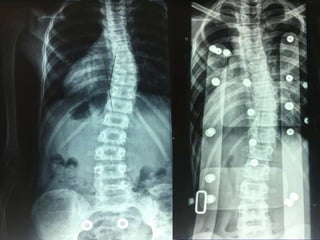

Double Spinal Deformity: a) Idiopathic

adolescent scoliosis

b) Spondylolysis - spondylolisthesis

Post operative correction